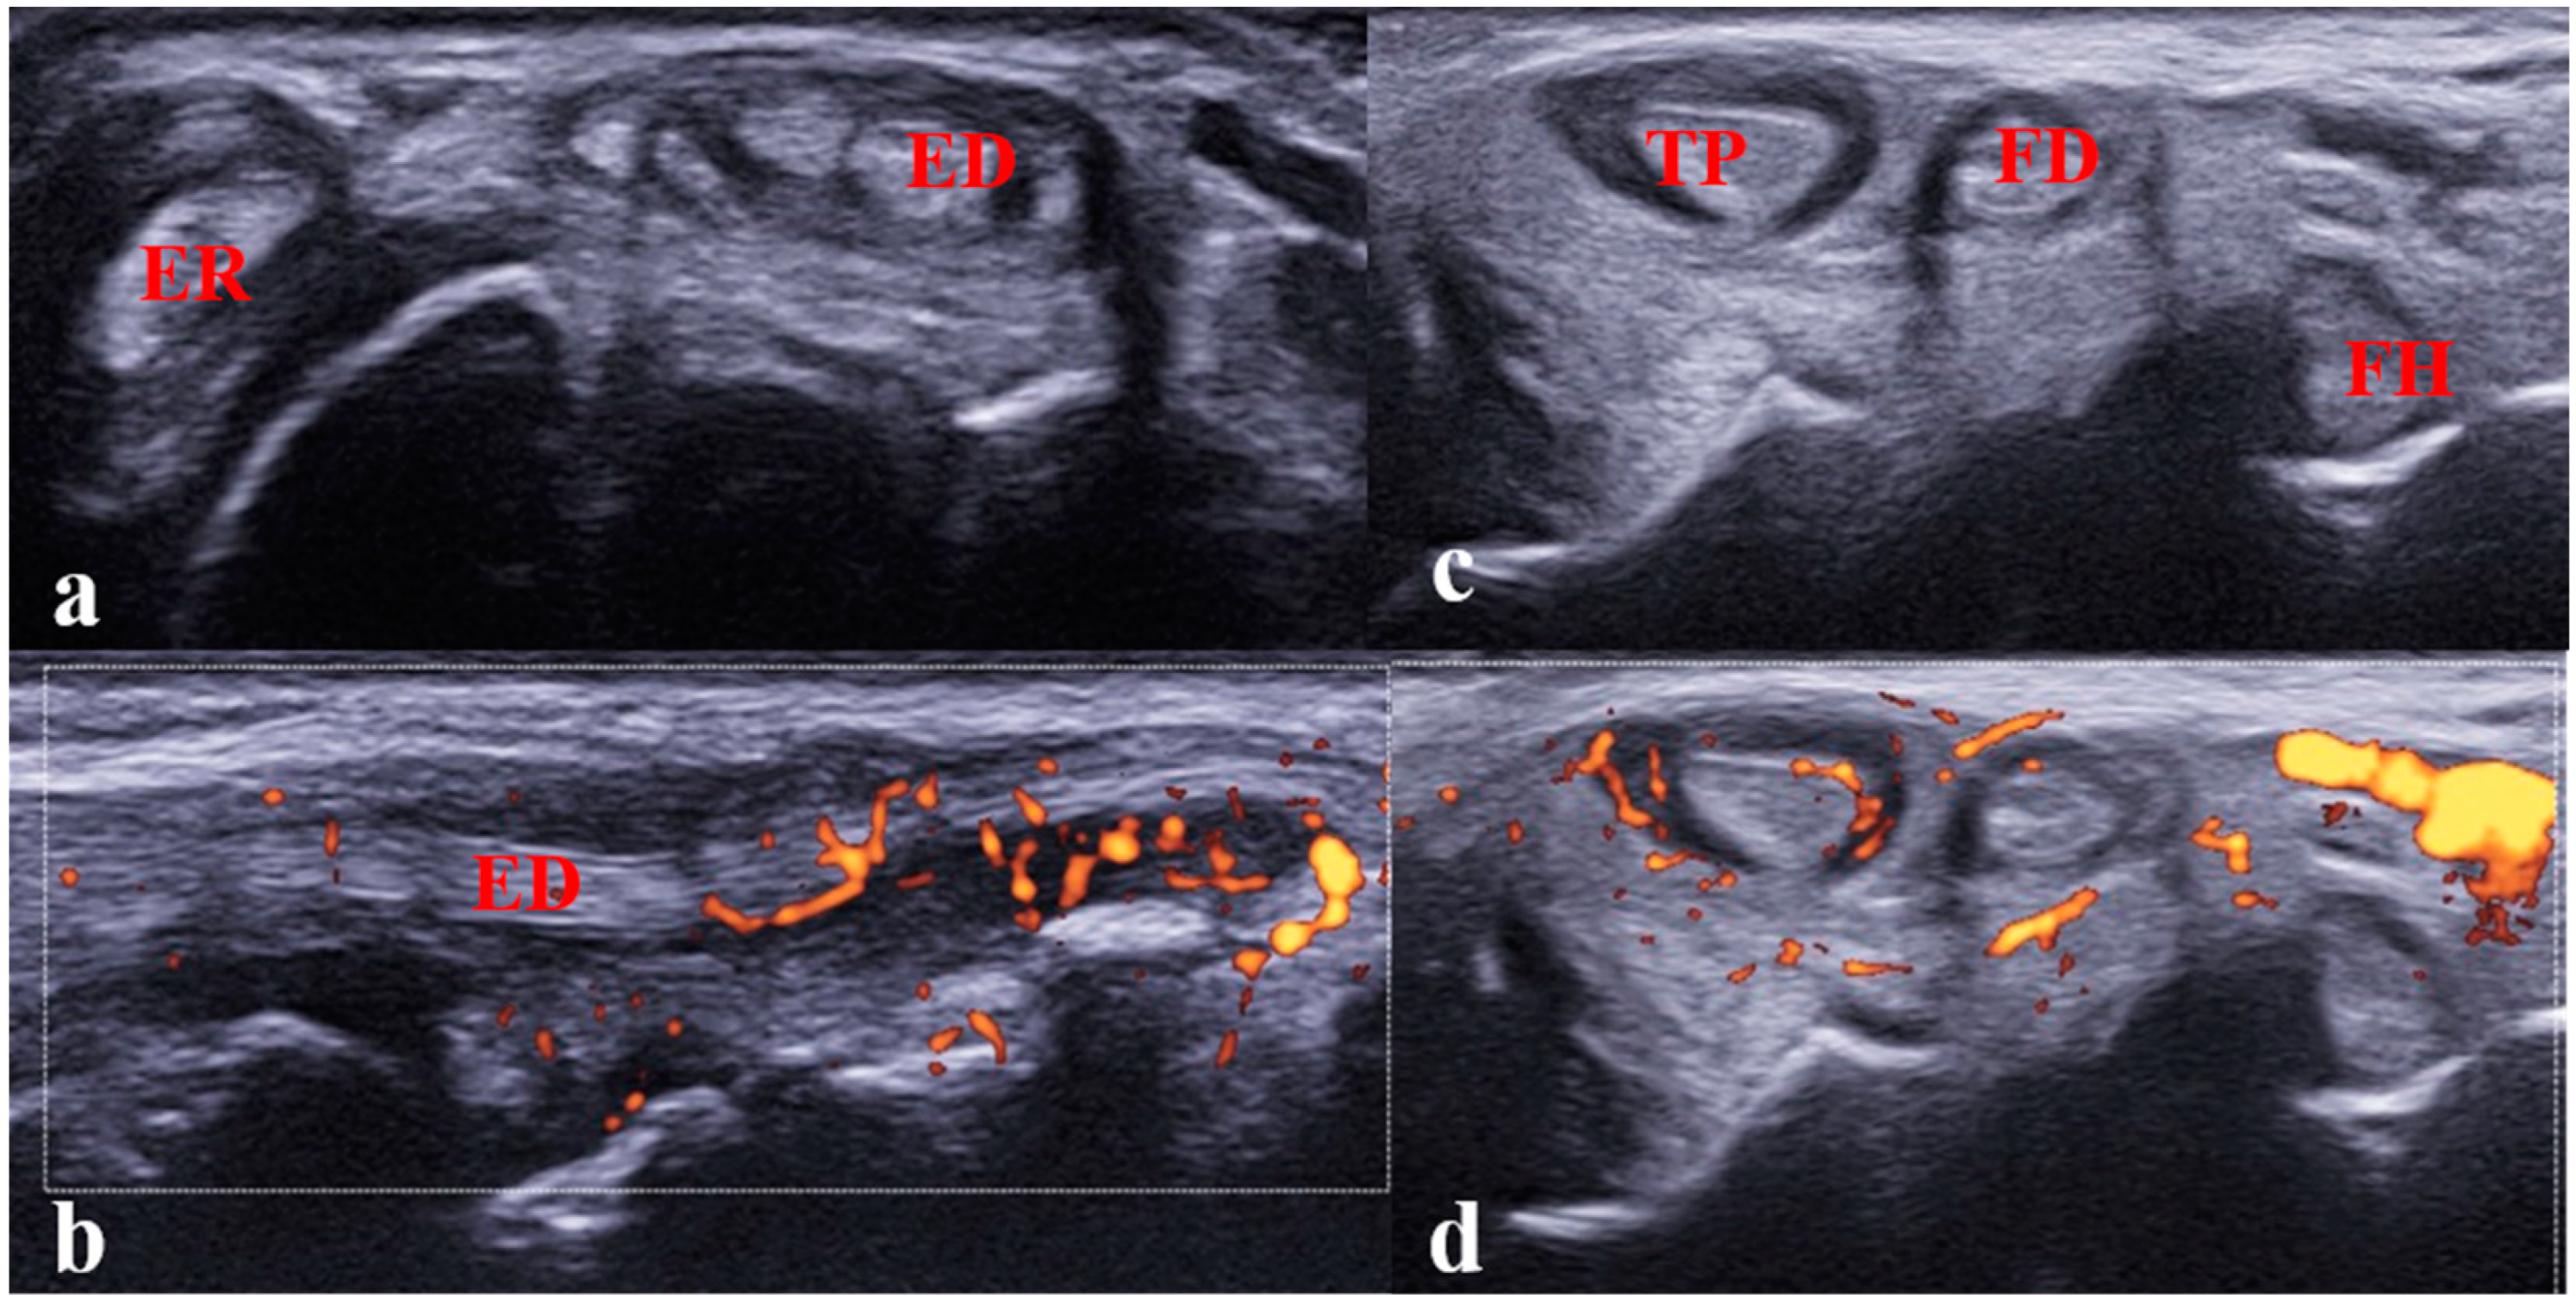

- Jousse-Joulin, S.; Breton, S.; Cangemi, C.; Fenoll, B.; Bressolette, L.; de Parscau, L.; Saraux, A.; Devauchelle-Pensec, V. Ultrasonography for Detecting Enthesitis in Juvenile Idiopathic Arthritis. Arthritis Care Res. 2011, 63, 849–855. [Google Scholar] [CrossRef]

- Weiss, P.F.; Chauvin, N.A.; Klink, A.J.; Localio, R.; Feudtner, C.; Jaramillo, D.; Colbert, R.A.; Sherry, D.D.; Keren, R. Detection of Enthesitis in Children with Enthesitis-Related Arthritis: Dolorimetry Compared to Ultrasonography. Arthritis Rheumatol. 2014, 66, 218–227. [Google Scholar] [CrossRef]

- Shenoy, S.; Aggarwal, A. Sonologic Enthesitis in Children with Enthesitis-Related Arthritis. Clin. Exp. Rheumatol. 2016, 34, 143–147. [Google Scholar]